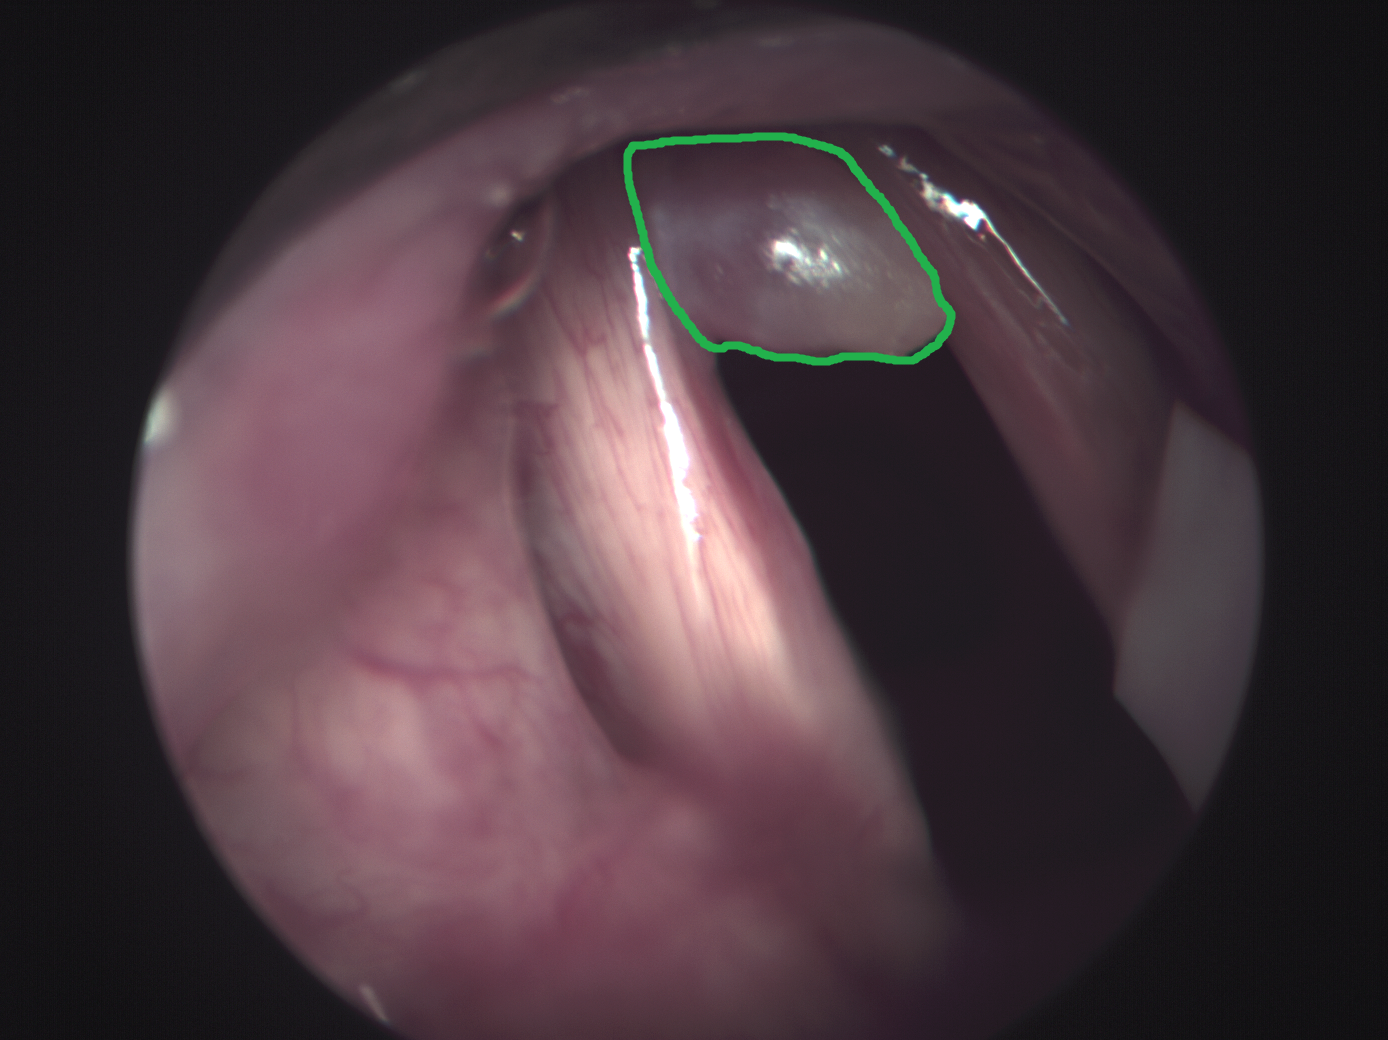

The data set consists of 98 patients, who were examined in a previous study due to mucous membrane abnormalities in the area of the upper aerodigestive tract [3]. Data acquisition was performed as described by Gerstner et al. [8] at the department of otorhinolaryngology at the University of Bonn. The study was approved by the local ethics committee (176/10 & 061/13, University of Bonn). The acquisition was performed throughout a normal procedure for diagnosis. An endoscopic device (Karl Storz GmbH & CoKG, Tuttlingen, Germany) was used for visual assessment. A Polychrome V monochromator (TillPhotonics, Gräfelfing, Germany) was used as light source for HSI and a monochromatic CCD-camera (AxioCamMRm, Carl Zeiss Microimaging GmbH, Göttingen, Germany) was employed for HSI data acquisition. The spectral bands range from to with a step size of and a bandwidth of . The spatial resolution is pixels. Biopsy samples were extracted from the imaged tumor areas, followed by histopathological evaluation. After the acquisition, we use the ImageJ-implementation of the SIFT-algorithm “Linear Stack Alignment with SIFT” [19] for aligning of the HSI images. Experts performed ground-truth annotation using RGB representations derived from the HSI images and the histopathological report. Note that this method induces some label noise as tumor outlines might be slightly inaccurate. In total, there are 83 patients with benign tumor region and 15 patients with malignant tumor region. Thus, the learning problem is particularly challenging due to extreme class imbalance. Tissue regions include the larynx, oropharynx and hypopharynx. Example images and highlighted tumor regions are shown in Figure 1. For model training and evaluation, we crop patches of size from the marked areas, including a margin towards the marked border. Overall, we obtain patches from all patients. For training and evaluation of our models, we define three subsets with a size of 19 patients (5 malignant / 14 benign) each and apply a cross-fold scheme. Note, data from one patient does not appear in different subsets. We split each subset into a test set (3 malignant / 8 benign) and validation set (2 malignant / 6 benign). We perform hyperparameter optimization using grid search on the validation splits and we report performance metrics for the test splits.